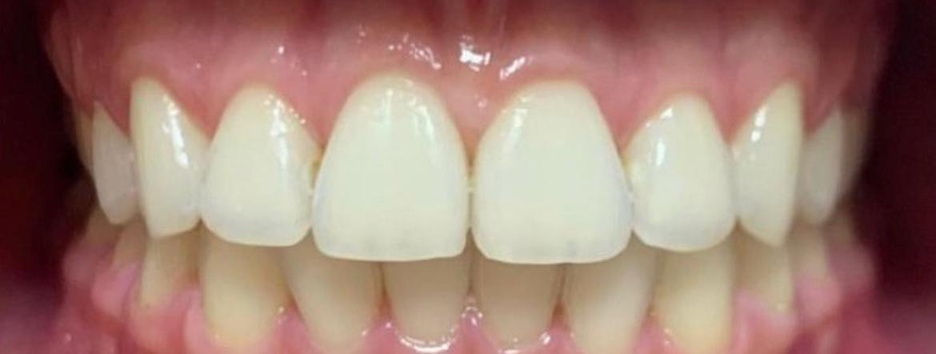

resina composta em dente anterior

curso de restaurações estéticas em resina composta

realidade clínica: resina composta